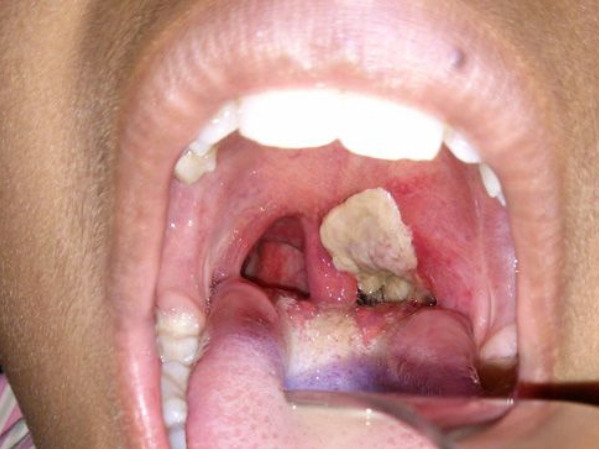

कैसे बनती है डिप्थीरिया में झिल्ली

डिप्थीरिया में शरीर के किसी भाग पर छद्म-झिल्ली का निर्माण हो जाता है। बैक्टीरिया से छोड़े गए जहर से जुड़े बेकार उत्पादों और प्रोटीन से एक झिल्ली बन जाती है जो कि बहुत ही महीन सी झिल्ली होती है जो सेल्स से चिपक जाती है और सांस लेने में परेशानी पैदा कर सकती है।